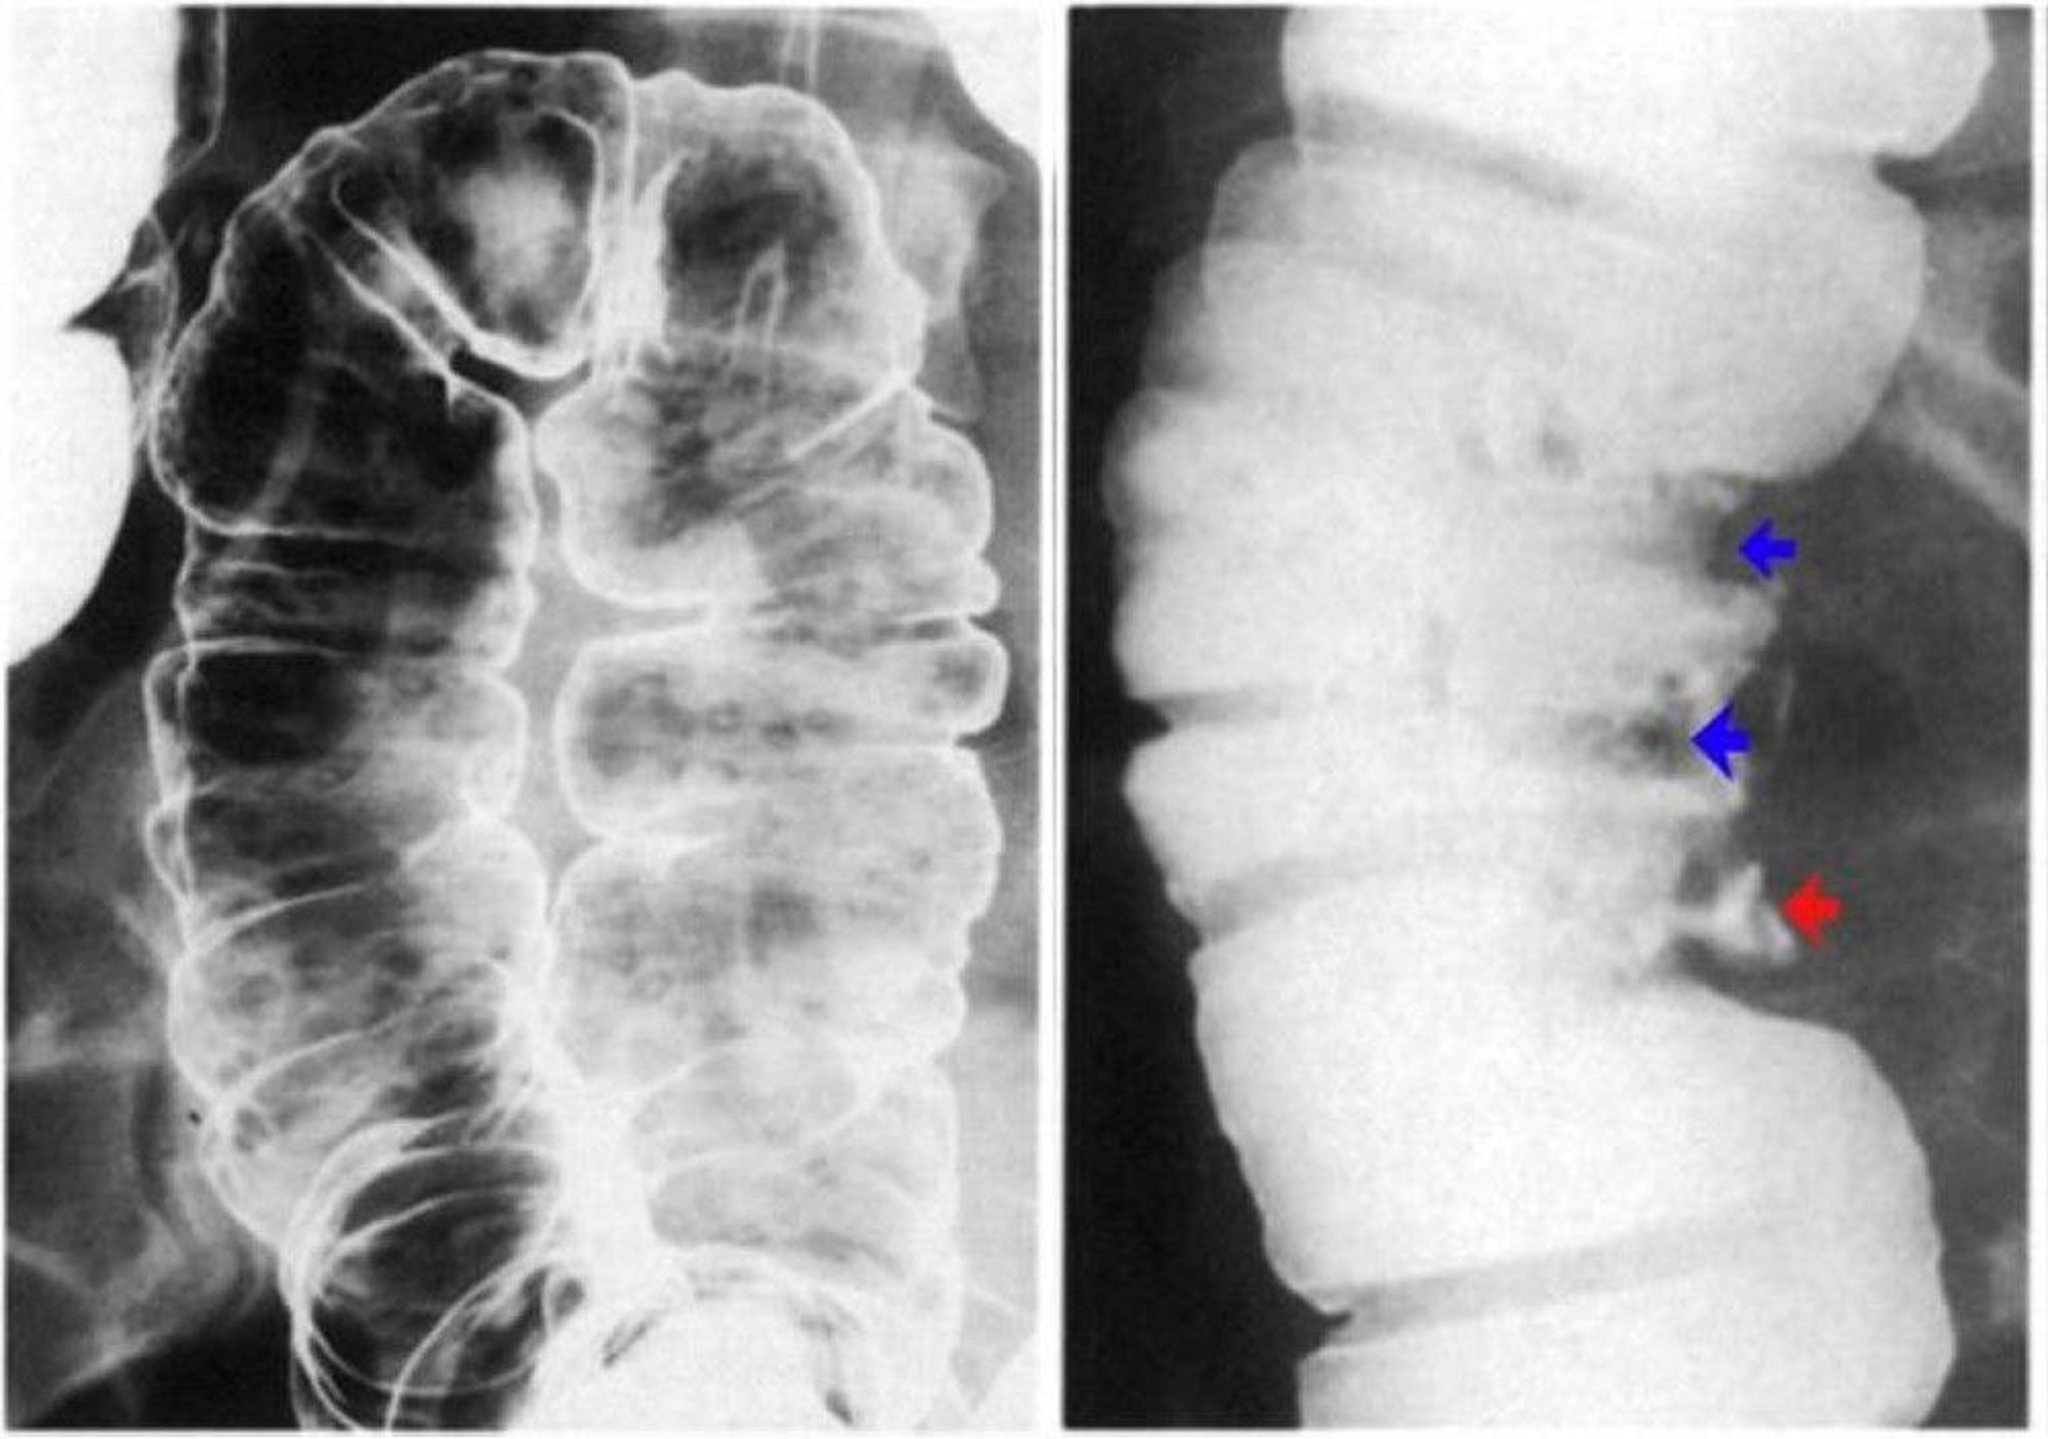

依然としてゾンデ法による小腸造影(enteroclysis)(逆行性小腸造影)の方が小腸をより詳細に観察できるが,軟性バルーンカテーテルで十二指腸挿管を行う必要がある。バリウム懸濁液を注入した後,小腸粘膜像を強調する二重造影剤としてメチルセルロース溶液を注入する。ゾンデ法による小腸造影は,大部分がCTまたはMRエンテログラフィーに取って代わられている。

これらは,希釈したバリウム懸濁液を用いたゾンデ法による単一造影の小腸造影画像である。空腸のスポット像(左),回腸のスポット像(中央),および回腸末端のスポット像(右)。